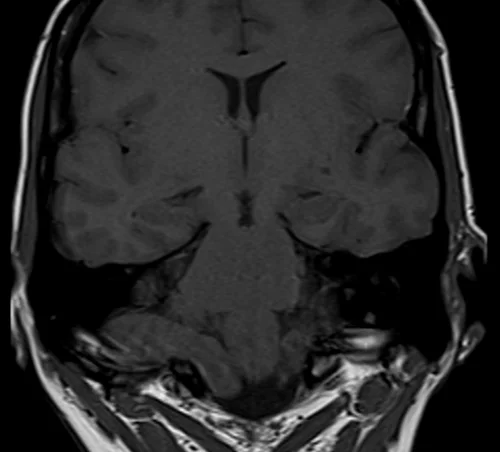

Brain epilipsy protocol mri coronal T1 images